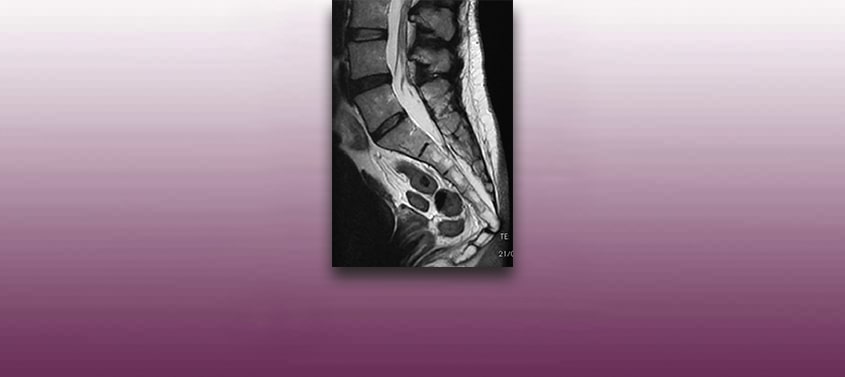

Spinale Stenose

Letzte Überarbeitung: 09/10/2018, Dr. med. Miguel B. Royo Salvador, Arztnummer: 10389. Neurochirurg und Neurologe. Der Begriff der Spinalkanalstenose bezeichnet eine verschleißbedingte Verengung des Wirbelsäulenkanals und einer hierdurch verursachten Bedrängung des darin liegenden Rückenmarkes. Die häufigste Ursache ist eine Arthrose, d.h. ein Verschleiß der Gelenke, Gelenkflächen und der Gelenkbänder. Die sich schleichend entwickelnde Instabilität der Wirbelsäule […]